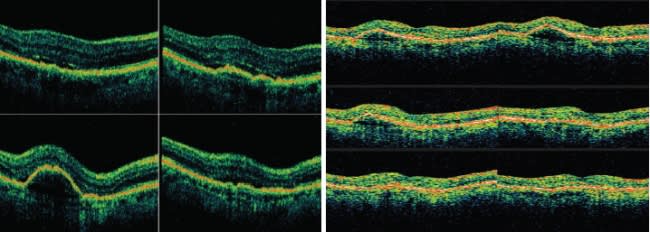

Studies such as these and our experience imaging more than 1000 patients with both time domain and SD-OCT have convinced us that SD-OCT is the new standard of care. We no longer feel comfortable treating patients without the additional information it provides. We expect the technology to continue to impact many areas, including vitreoretinal interface disease, glaucoma, management of neovascular agerelated macular degeneration (AMD) (Figures 4 and 5), explaining the cause of vision loss (Figure 6), and (with advances in software) measuring the effects of therapy.

Figures 4 and 5. Spectral domain OCT (left) revealed persistent subretinal fluid in this patient undergoing treatment with ranibizumab (Lucentis). Fluid was not easily detected with time domain OCT (right).